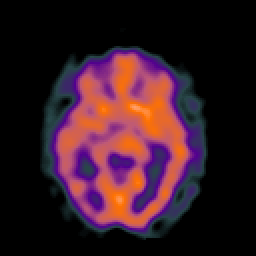

SPECT TC Study #2 -- Slice #25

[Home][Help][Clinical][Tour 1][Tour 2][Tour 3] Slice 25